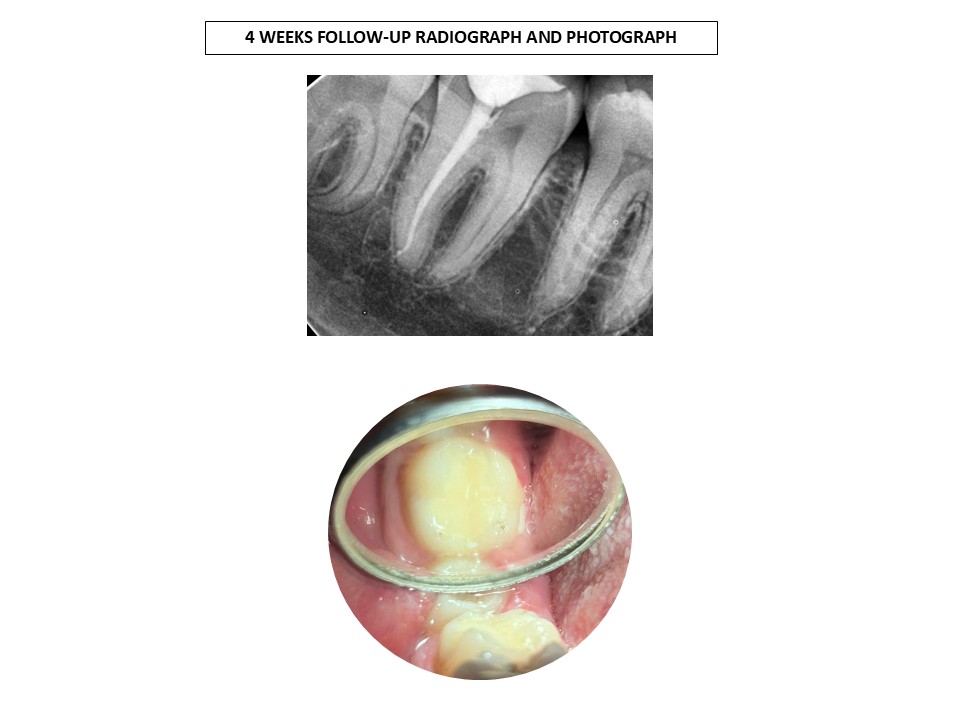

A total of 139 students competed in the south zone in the biodentine case competition for dental students. Dr Joselin Rosary is one among 139 participants to secure this coveted prize, due to the ingenuity of the endo vital therapy she performed in the Outpatient department of Madha Dental College.